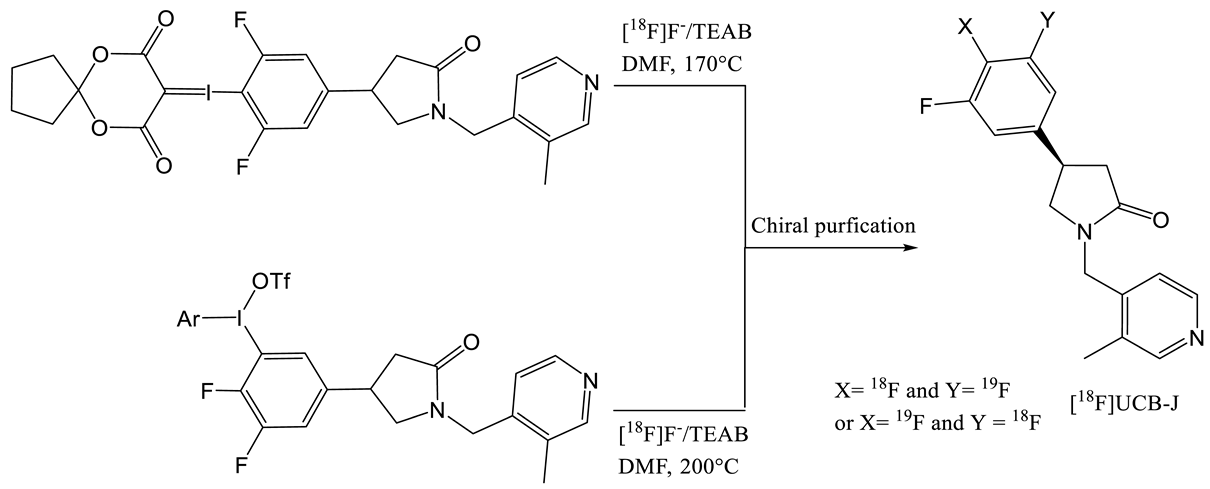

2. Radiochemistry of SV2A PET Radiotracers

- Li, S.; Cai, Z.; Zhang, W.; Holden, D.; Lin, S.-F.; Finnema, S.J.; Shirali, A.; Ropchan, J.; Carre, S.; Mercier, J.; et al. Synthesis and in vivo evaluation of [18F]UCB-J for PET imaging of synaptic vesicle glycoprotein 2A (SV2A). Eur. J. Nucl. Med. Mol. Imaging 2019, 46, 1952–1965. [Google Scholar] [CrossRef]

- Li, S.; Cai, Z.; Wu, X.; Holden, D.; Pracitto, R.; Kapinos, M.; Gao, H.; Labaree, D.C.; Nabulsi, N.; Carson, R.E.; et al. Synthesis and in Vivo Evaluation of a Novel PET Radiotracer for Imaging of Synaptic Vesicle Glycoprotein 2A (SV2A) in Nonhuman Primates. ACS Chem. Neurosci. 2018, 10, 1544–1554. [Google Scholar] [CrossRef]

- Constantinescu, C.C.; Tresse, C.; Zheng, M.; Gouasmat, A.; Carroll, V.M.; Mistico, L.; Alagille, D.; Sandiego, C.M.; Papin, C.; Marek, K.; et al. Development and In Vivo Preclinical Imaging of Fluorine-18-Labeled Synaptic Vesicle Protein 2A (SV2A) PET Tracers. Mol. Imaging Boil. 2018, 21, 509–518. [Google Scholar] [CrossRef]

| Entry | Tracer | Ref | Synthesis of the Radiotracer | pIC50 for Human SV2A | Ki (nM) for Human SV2A | Molar Activity (GBq. µmol−1) | RCY (%) |

|---|---|---|---|---|---|---|---|

| 1 | [11C]Levetir-acetam | [18] |  | 5.7 [24] | 2500 | 17 | 8.3 (dc) |

| 2 | [18F]UCB-H | [19] |  | 7.8 | 9.0 | 518 | 15 (ndc) |

| 3 | [21] |  | 815 ± 185 | 35 (ndc) | |||

| 4 | [18F]UCB-A | [23] |  | 7.9 [24] | ND a | 65 | 14 (dc) |

| 5 | [11C]UCB-J | [24] |  | 8.2 | 1.5 | 215 | 35 (dc) |

| 6 | [18F]UCB-J | [27] |  | Similar to [11C]UCB-J | Similar to [11C]UCB-J | 59 ± 36 | 1–2 (ndc) |

| 7 | [18F]SynVesT-1 | [28,29] |  | 8.4 | 2.2–4.7 b | 242 | 19 (ndc) |

| 8 | [18F]SynVesT-2 | [31] |  | ND a | 12 | 141 | 7(dc) |

| 9 | [18F]1 | [33] |  | 8.3 | ND a | 40–80 | 1.5 (dc) |